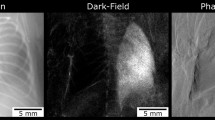

As shown in Fig. 1, x-ray dark-field radiograms, in contrast to conventional x-ray transmission projections, were able to visualize changes in the neonatal mouse lung induced by MV-O2. Unventilated lungs from animals breathing room air appear bright, whereas the diseased lungs display a reduced dark-field signal intensity, due to reduction in air-tissue interfaces. Histology supported the dark-field imaging results with larger and fewer alveoli in the lungs of neonatal mice undergoing MV-O2 (Fig. 1(C)). Dark-field radiograms furthermore showed an increase in signal heterogeneity in neonatal mice undergoing 8 hours of MV-O2 (Fig. 2), which, apart from the overall signal decay, reflects inhomogeneity in lung injury and consecutive remodeling.

Contrary to conventional x-ray transmission (A) that reveals only hardly appreciable differences, dark-field (B) radiograms yield a clear discrimination in terms of signal intensity between the lungs from animals in the room air (RA) group as compared to neonatal mice undergoing MV-O2 for 8 h. (C) The corresponding histological sections. Scale bars for radiographies correspond to 5 mm and for histology to 100 μm.